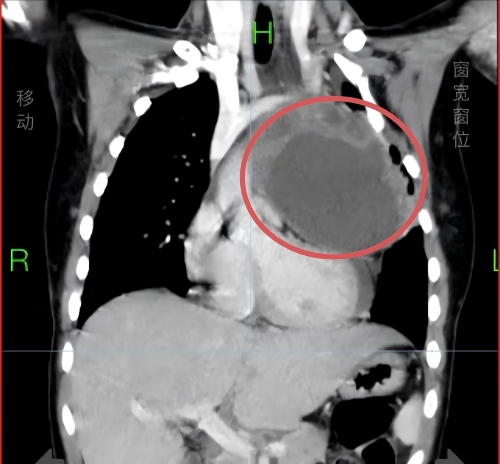

48岁那年,一次同事间的澡堂闲聊,让他发现自己的肚子大得异常。49岁,被确诊酒精性肝硬化伴腹水,他万念俱灰,只想“死了算了”。如今,18年过去了,长沙67岁的老李在经历了47次住院,数次与死神交手,遭遇肝源性糖尿病、肺动脉高压等并发症的连环挑战后,眼睛里却满是希望。3月2日,他从湖南省人民医院肝病内科出院,打算遵医嘱半个月后到心内科肺动脉高压门诊就诊。